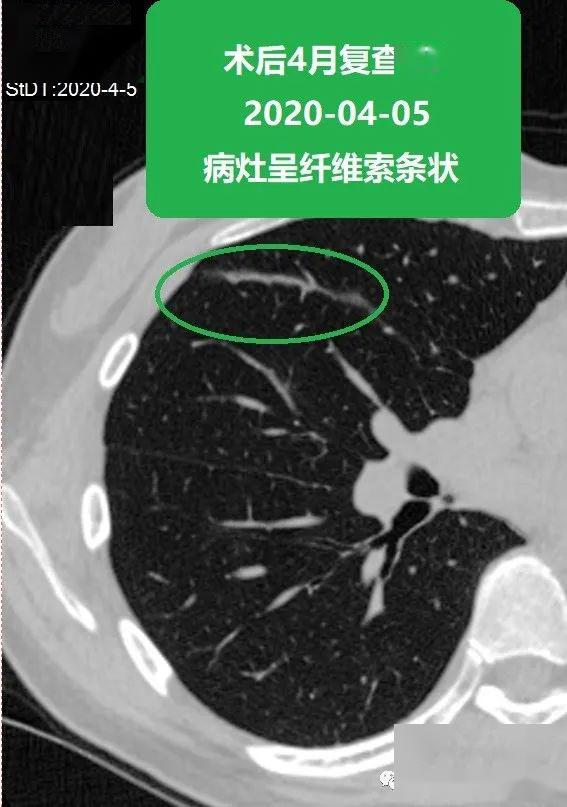

苏大附二院靳勇医生团队病例分享第51期肺磨玻璃结节的消融